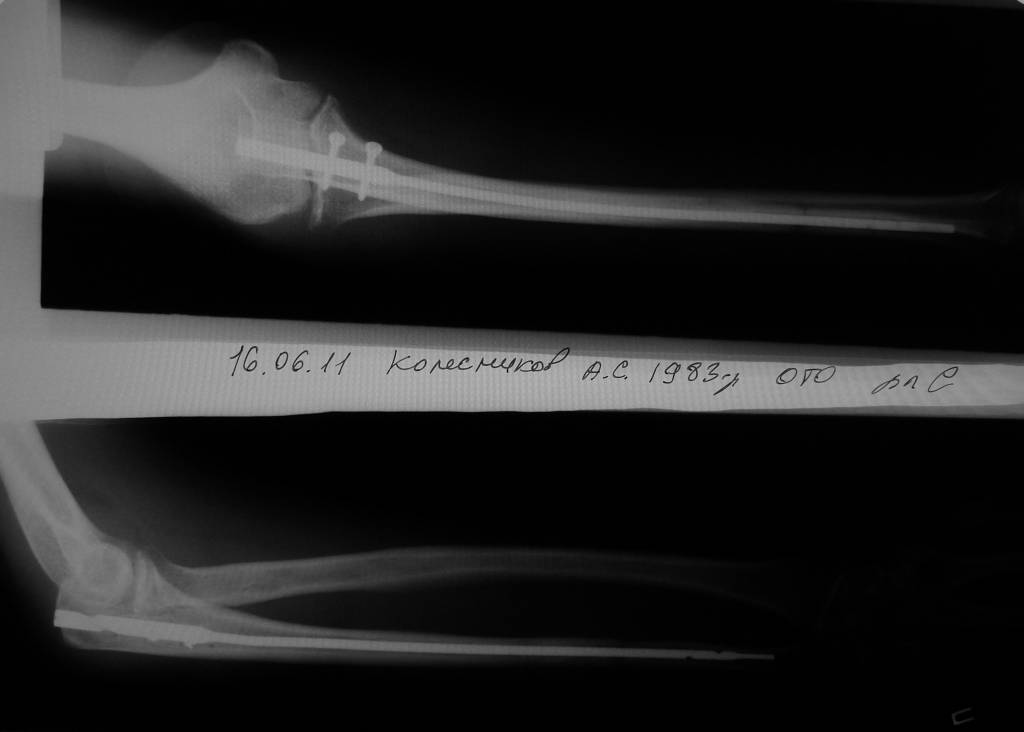

6 февраля 2011 года сломал локтевую кость со смещением. Поставили аппарат Илизарова. Вместо двух месяцев проносил четыре, срасталось медленно. Сняли, сказали разрабатывать и через 5 дней кость сместилась опять. 15 июня сделали вторую операцию, поставили дорогой стержень в кость, закрепили в области локтя на два шурупа. Перелом у меня в 1/3 ближе к кисти. Вторую часть кости одели на стержень, но не закрепляли. Также освежили концы костей, так как они зарубцевались и костномозговые каналы полностью закрылись.Месяц проносил лангету до плеча, потом сказали разрабатывать руку, но постепенно я начал чувствовать шевеление в месте перелома и щас чувствую.Щас опять хотят загипсовать уже всю руку на 2 месяца, но мне кажется что концы костей опять зарубцевались за 2 месяца зарастания "впустую" и даже в гипсе уже не срастется.По снимкам щель отчетливо видна. На руке вместе перелома нащупывается шишечка. Предположительно, что 1/3 кости, которая не прикручена к стержню, имеет хождение вдоль стержня.Кисти еще после аппарата Илизарова не поворачивается ладонью вверх и вниз. Имеет ход градусов 15 влево вправо и все.Что мне делать? Как еще восстановить руку? Еще одна операция? Исправит ли гипс на 2 месяца проблему? Мне 28 лет.

По этому снимку ничего плохого не видно. Нужна и вторая проекция. Когда сделан снимок?

Фиксация стержнем в первую очередь должна обеспечить возможность разработки движений, поскольку гипсовая иммобилизация при этом не нужна.

Действительно, гипсовая повязка может усугубить трудности с движениями, не решив проблему со сращением.

Для того, чтобы предложить конкретный план выхода из этой ситуации, нужно более точное представление о проблеме - надо хотя бы увидеть свежие рентгенограммы всего предплечья в двух проекциях.